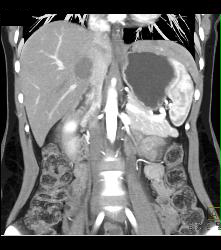

Patent Popliteal Artery and Trifurcation